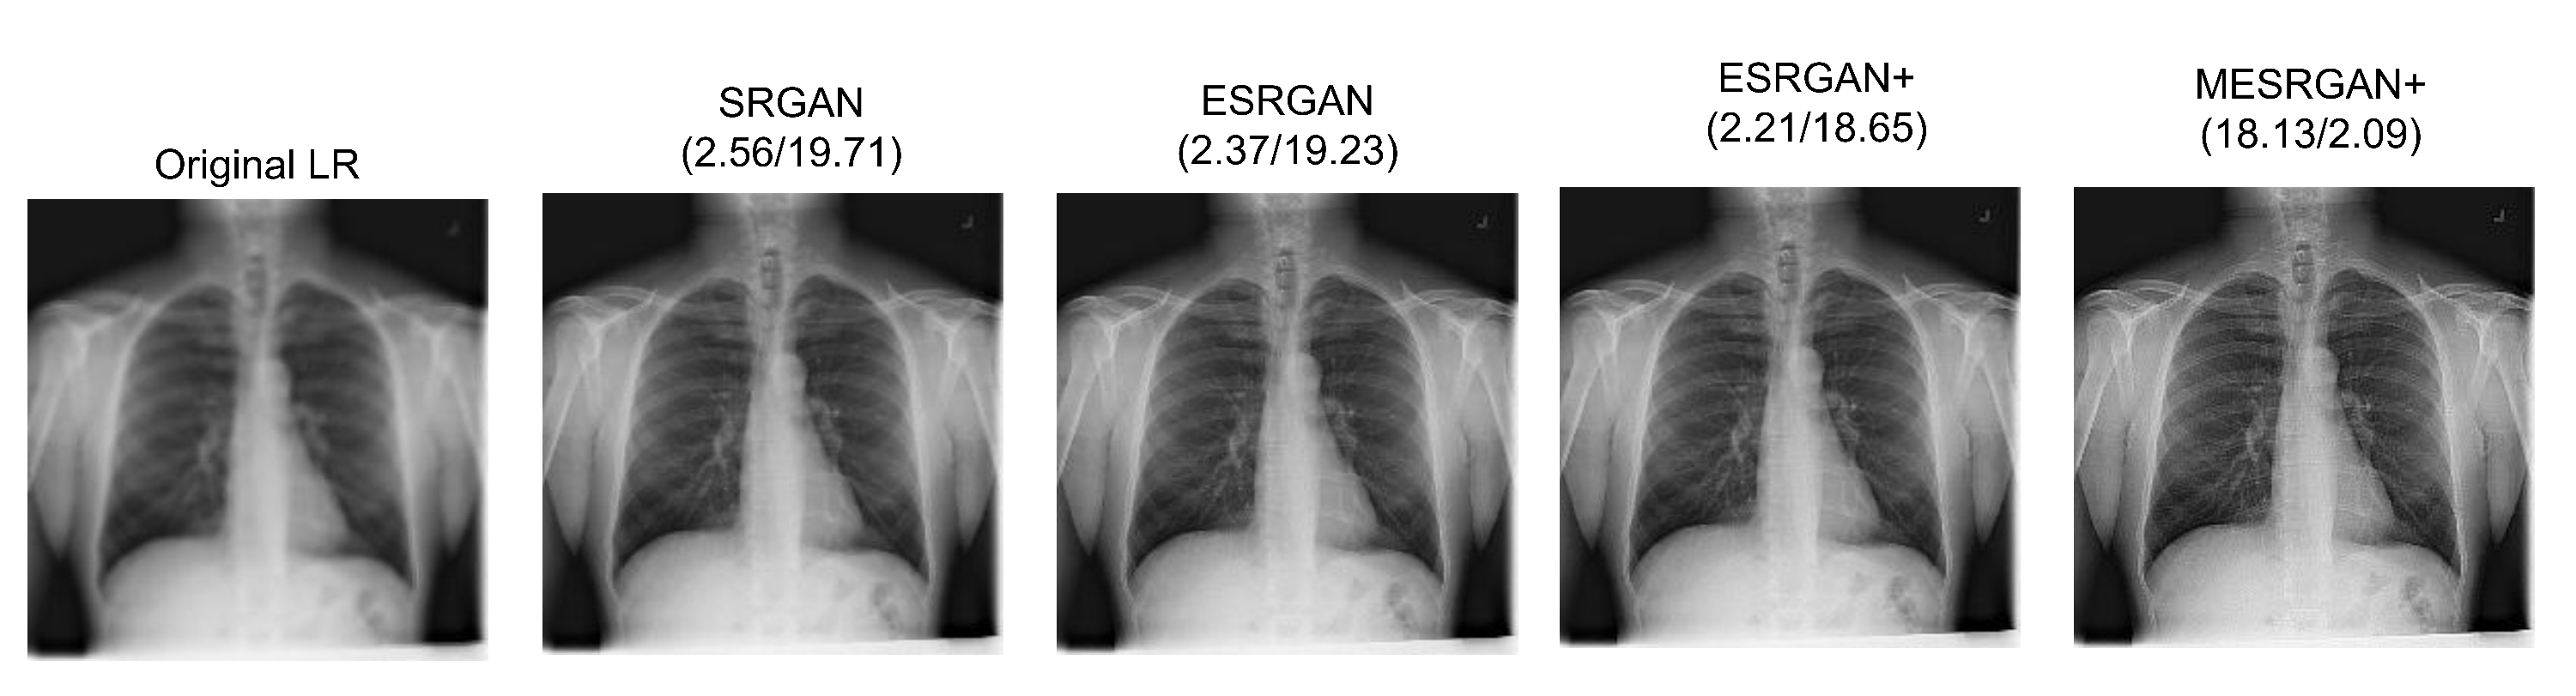

| Parameter | SRGAN | ESRGAN | ESRGAN+ | MESRGAN+ |

|---|---|---|---|---|

| Residual block of the generator | Conv(3, 64, 1) Batch norm ReLU Conv(3, 64, 1) Batch norm | Conv(3, 64, 1) ReLU Conv(3, 64, 1) | Conv(3, 64, 1) ReLU Conv(3, 64, 1) | Conv(3, 64, 1) ReLU Conv(1, 64, 1) ReLU Conv(3,64,1) ReLU Conv(3, 64, 1) |

| Input size | LR | LR | LR | LR |

| PSNR | 19.71 dB | 19.23 dB | 18.65 dB | 18.12 dB |

| PI | 2.56 | 2.37 | 2.21 | 2.09 |